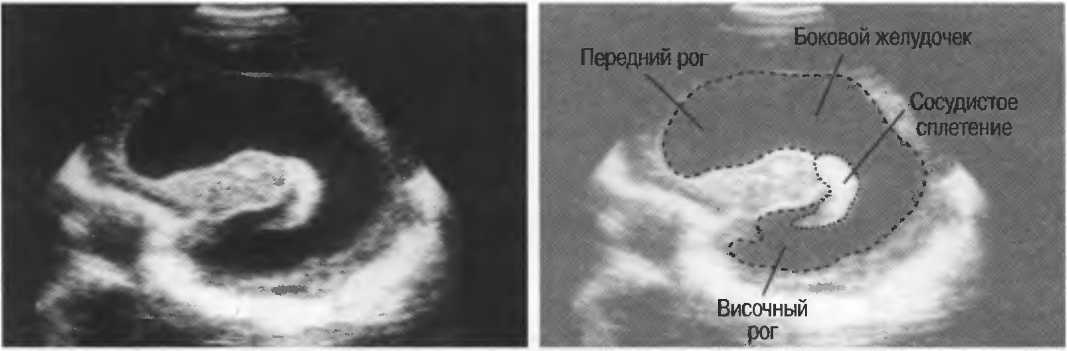

3. Ультразвуковые исследования в педиатрии. Для детей необходим датчик с частотой 5 МГц с глубиной фокусировки на 5-7 см. При исследовании мозга новорожденного используется секторный датчик с частотой 7,5 МГц с глубиной фокусировки на 4-5 см (этот датчик также используется для исследования яичек и структур шеи у взрослых).